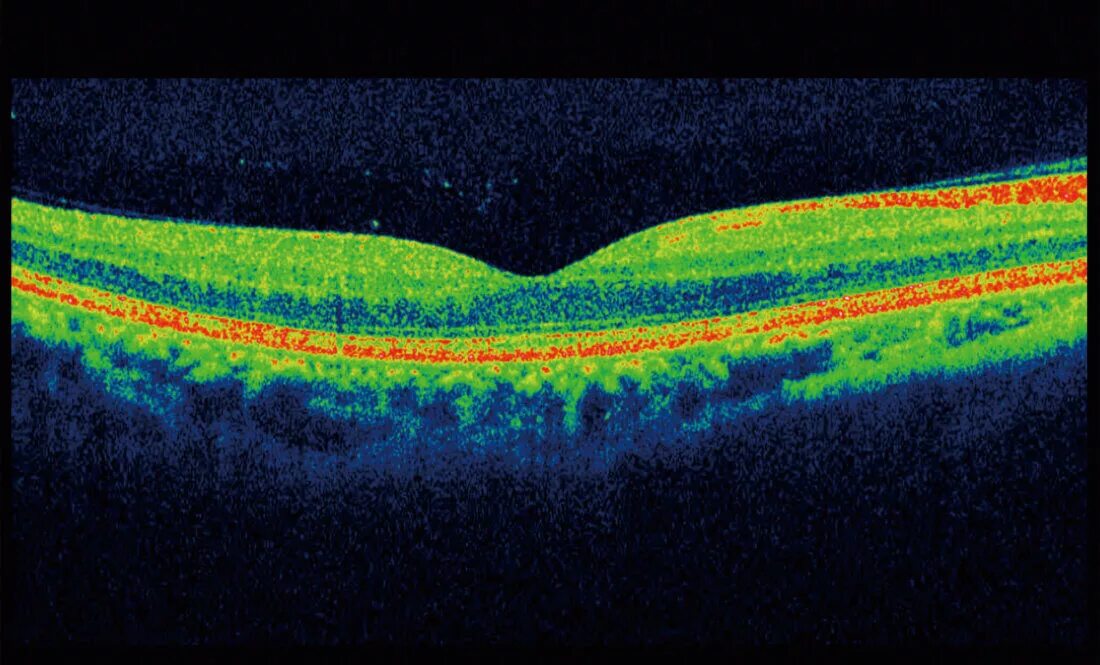

Когерентная томография сетчатки